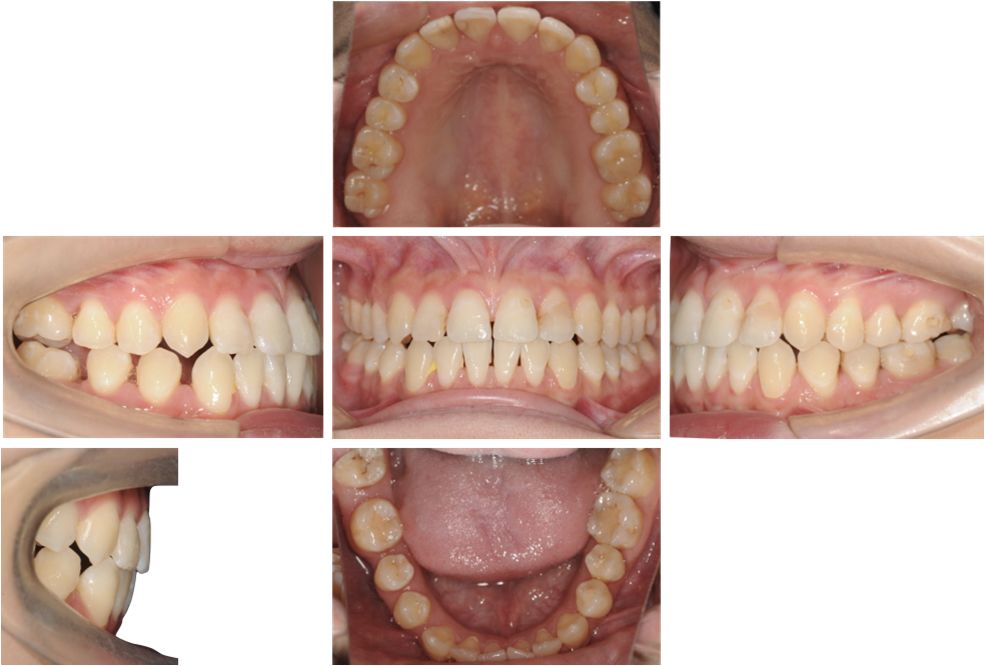

矫治中

第8副,矫治器与牙面贴合,矫治过程中配合III类牵引,有利于尖牙、磨牙关系的改善。

第20副,矫治器与牙面贴合,近中矩形附件使矫治器对47牙有较好的固位,47牙与45相对移动,磨牙尖牙关系改善。